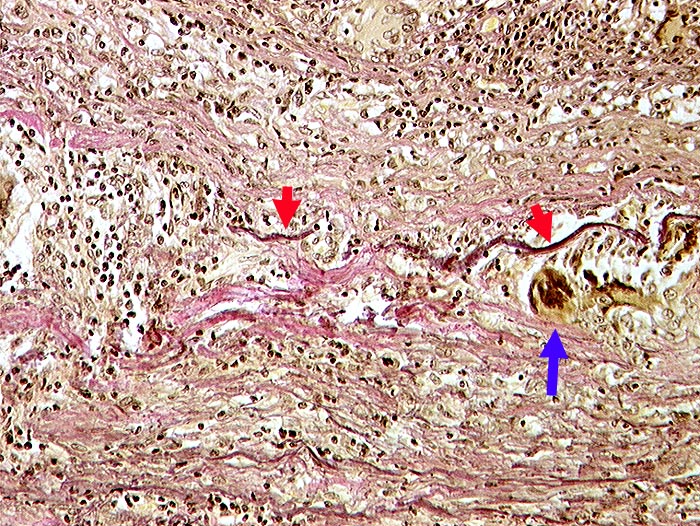

Riesenzellarteriitis der Arteria carotis interna

Dichtes lymphohistiozytäres Entzündungsinfiltrat in der Gefässwand. Riesenzellen phagozytieren die bereits fragmentierte Lamina elastica externa.

Primäre Vaskulitis mit Befall grosser Gefässe, bevorzugt extrakranielle Äste der Arteria carotis. Temporalarterie häufig betroffen.